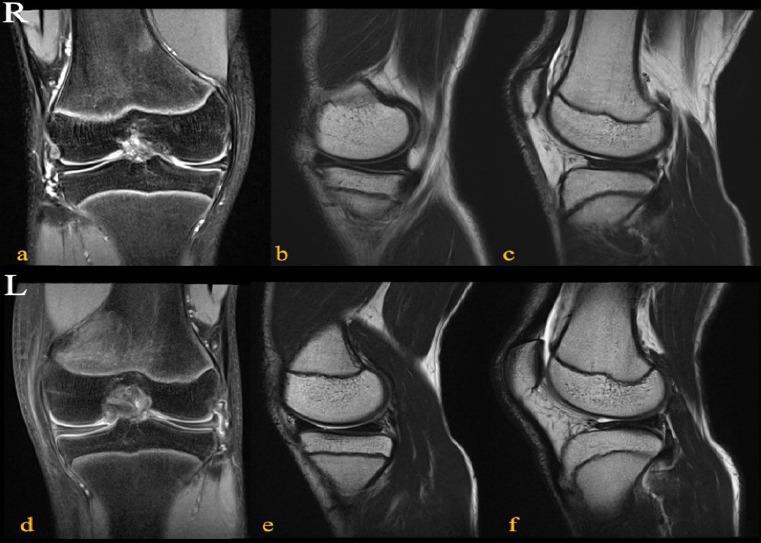

A 14-year-old boy who developed left knee pain after twisting his knee at school was referred to our hospital. He had limited extension of -10°, lateral clicking, and pain on the McMurray test in the left knee and complained of slight clicks in the right knee. Magnetic resonance imaging results for both knees revealed discoid medial and lateral menisci. Surgery was performed on the symptomatic left knee. Arthroscopically, a Wrisberg-type discoid lateral meniscus and an incomplete-type medial discoid meniscus were confirmed. The symptomatic lateral meniscus was saucerized and sutured and only the asymptomatic medial meniscus was observed. The patient was doing well 24 months after surgery.

一名14岁男孩在学校扭到膝盖后出现左膝疼痛,被转诊至我院。他左膝伸展受限达-10°,有外侧弹响,麦氏试验时疼痛,右膝有轻微弹响。双膝磁共振成像结果显示双侧盘状内侧和外侧半月板。对有症状的左膝进行了手术。关节镜检查证实为Wrisberg型外侧盘状半月板和不完全型内侧盘状半月板。对有症状的外侧半月板进行了修整和缝合,仅观察无症状的内侧半月板。术后24个月患者情况良好。